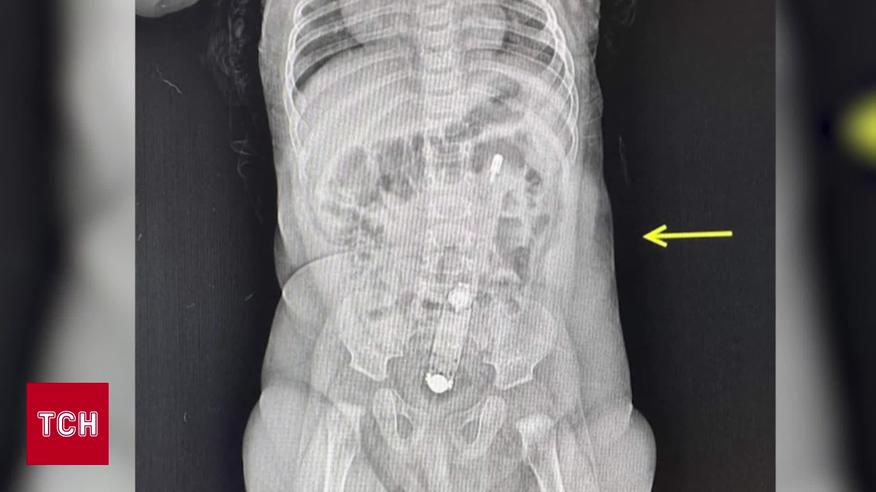

У Луцьку медики діставали термометр із кишківника піврічної дівчинки. У лікарню до медиків звернулася мати немовляти. Пояснила: в дитини був закреп, скористатися термометром їй, начебто, порадили в Мережі. Медики спочатку не повірили, але згодом побачили термометр на рентгені. І дитину таки довелось оперувати. Як вона почувається – дивіться в сюжеті журналістки ТСН Тетяни Хомич.